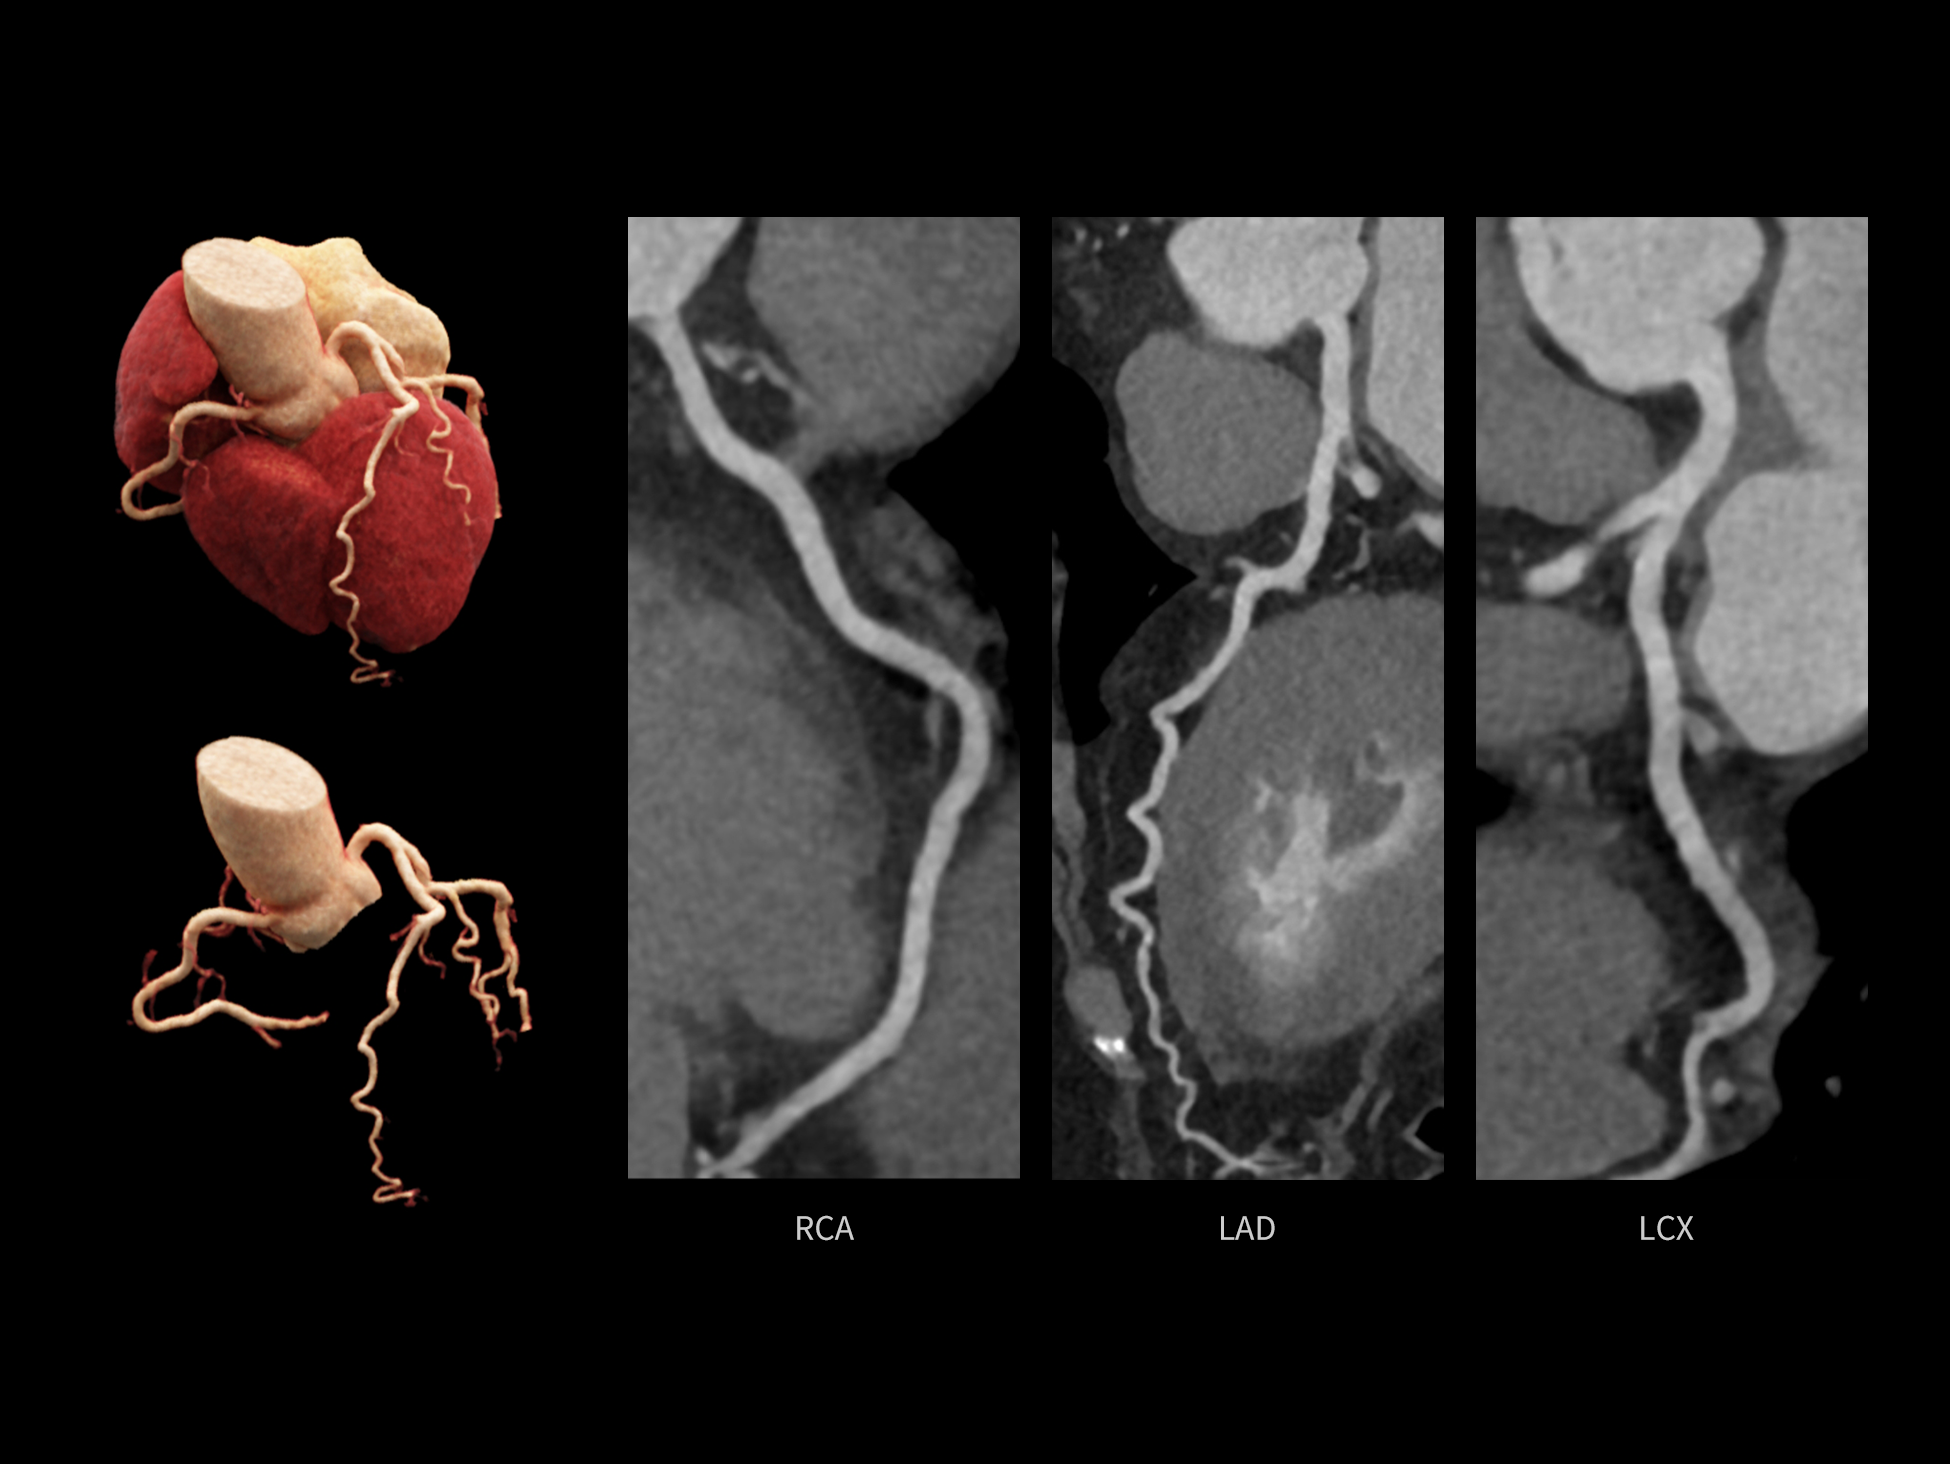

CardioCapture 2.0 通过“识别–追踪–建模–校正”的完整流程,精准分割心脏结构,动态追踪运动轨迹,并构建多时相运动场,最终实现冠脉、瓣膜、心肌及心室结构的同步校正,清晰洞见每一次心跳细微变化,真正将心脏动态掌握于毫秒之间。

CardioCapture 2.0 在目标时相前后重建多时相影像,通过深度学习网络精准提取冠脉中心线,进而建立时相间运动模型,实现对冠脉分段图像的精准运动校正。

CardioCapture 2.0 可对心肌、瓣膜及心室等结构进行同步运动校正。基于深度学习的心脏精细分割,实现了更完整的心脏全局信息提取,能有效抑制全心运动伪影,显著提升心脏细节的清晰度与诊断可靠性。

冠脉运动校正

全心结构运动校正

心脏成像,自由掌控

uCT SiriuX® 以 8ms 全心等效时间分辨率与16cm宽体覆盖,突破传统心脏成像局限,完整呈现搏动中的心脏结构与动态功能;配合无心电门控扫描与智能化工作流,更使心脏检查摆脱心率、配合度与操作复杂度的束缚,实现真正自由从容的成像体验,为临床功能评估提供更深层依据。